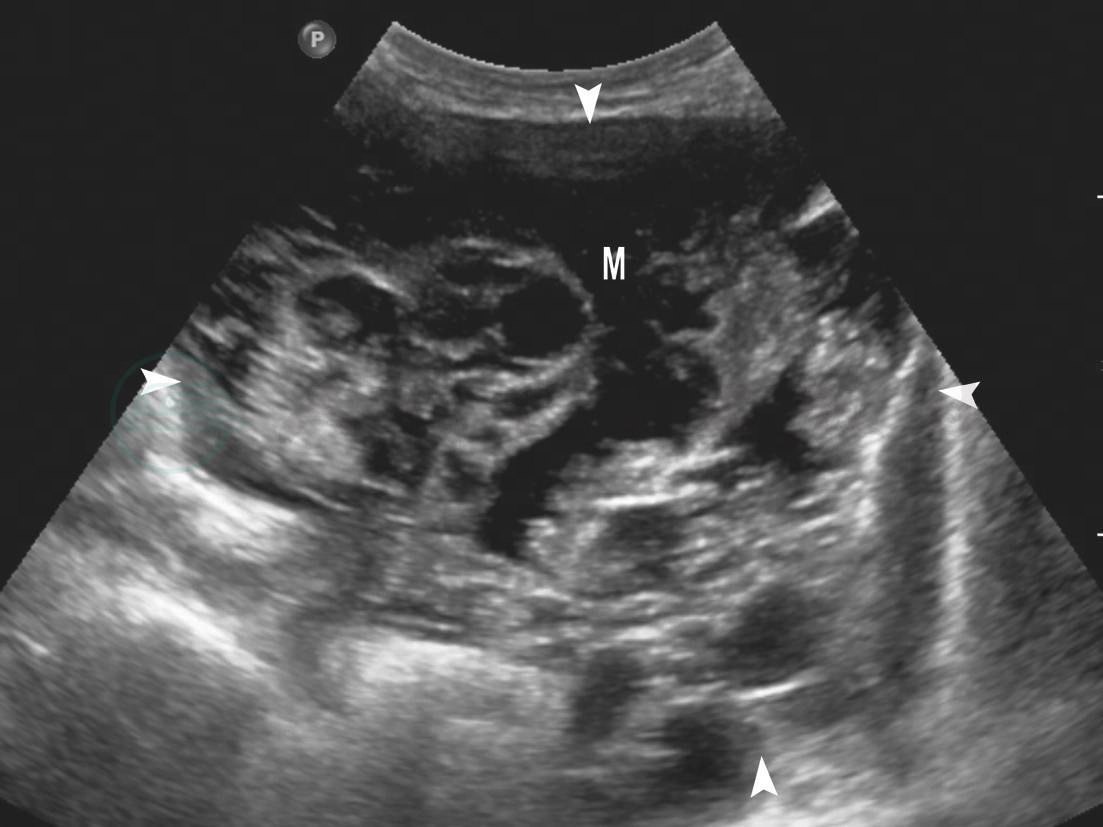

肿块多为囊实性,可呈囊性或实性为主或囊实各半,类圆形或椭圆形,形态可不规整,囊壁厚薄不均,囊腔内有乳头或菜花样实性回声突起,内部回声实性与囊性夹杂,回声杂乱(图7-16,图7-17);实性为主肿块往往形态不规整,椭圆形或肾形,包膜大多完整,内部回声杂乱不均匀,回声强弱不等,在实性回声中夹有大小不一、类圆形或不规则形的无回声区(图7-18)。除肿瘤本身的表现外,盆腹腔内腹水征是恶性卵巢肿瘤的常见合并征象。以囊实性回声为特征的恶性卵巢肿瘤包括:浆液性囊腺癌和黏液性囊腺癌、未成熟畸胎瘤和成熟型畸胎瘤恶变、子宫内膜样腺癌;以实性肿块为表现者包括:颗粒细胞瘤、无性细胞瘤、卵黄囊瘤、支持-莱狄细胞瘤、恶性Brenner瘤、恶性淋巴瘤、克鲁根勃瘤。

图7-18 恶性卵巢肿瘤声像(实性为主回声)

M:恶性卵巢肿瘤;箭头:恶性卵巢肿瘤边界不清

图7-17 恶性卵巢肿瘤声像(囊实性回声)